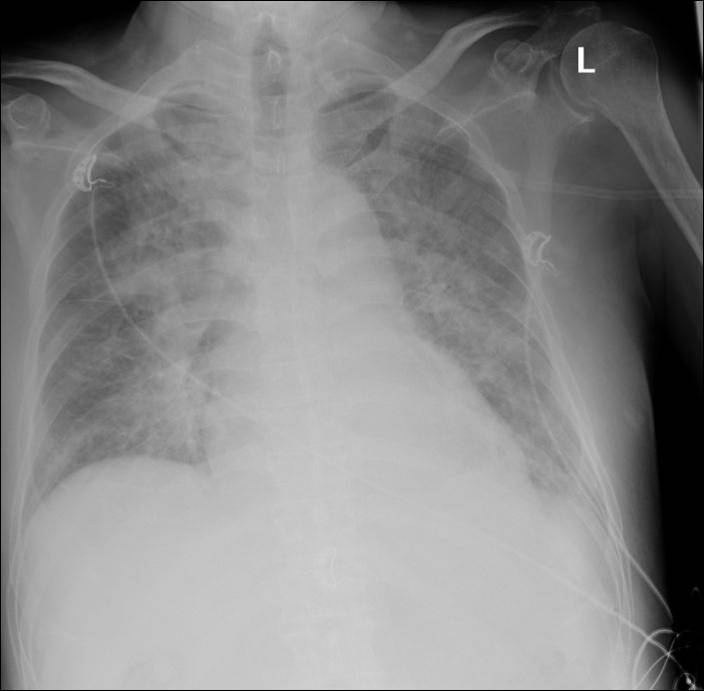

胸片

◆入院后反复心衰发作,不能平卧,腹胀,胸腔积液,双下肢浮肿

超滤治疗效果-肺水肿减轻